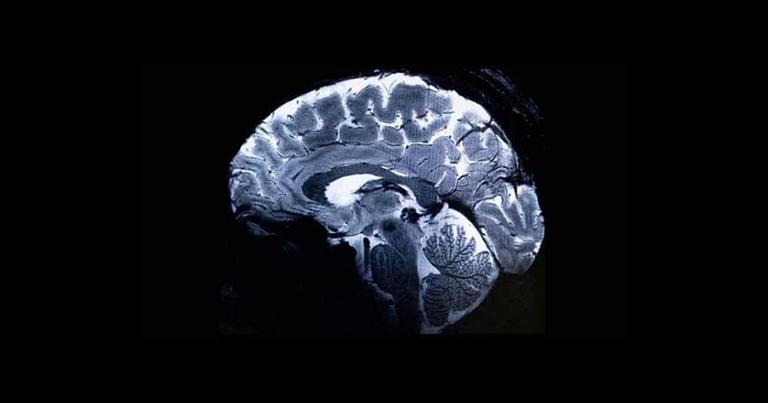

The world's most powerful MRI scanner has unveiled the first-ever images of the human brain, promising unprecedented insights into its complexities and associated afflictions.

Physicist Alexandre Vignaud, a key member of the research team, expressed his enthusiasm, stating, "We have seen a level of precision never reached before at CEA." Unlike conventional MRIs, which typically operate at around three teslas, this extraordinary MRI machine, affectionately nicknamed Iseult, boasts an impressive 11.7 teslas, resulting in images of the human brain with ten times more precision.

"With this machine, we can see the tiny vessels which feed the cerebral cortex, or details of the cerebellum which were almost invisible until now," explained Vignaud.

The MRI machine is housed within a cylindrical structure measuring five meters in both length and height and is powered by a massive 132-ton magnet. Its capabilities are further enhanced by a coil conducting a current of 1,500 amps. Despite its immense power, the machine features a three-foot opening to accommodate human subjects.